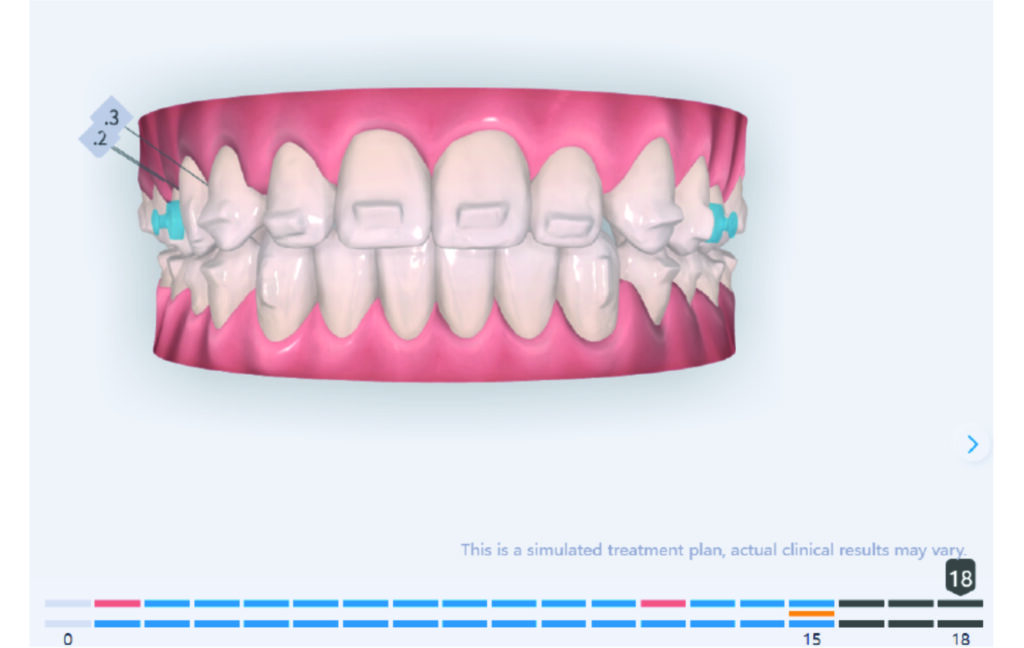

A 1.5 mm deviation of the upper dental midline to the patient’s left was noted, along with a slight mandibular midline shift to the right, likely due to asymmetrical mandibular growth observed in the facial structure. Severe mesial rotations of teeth 16 and 26 were evident in the initial records. As derotation of 16, 26, 17, and 27 progressed up to aligner 16, the premolars in segments I and II moved distally, resulting in a bilateral Class I relationship, as intended in the initial treatment plan.

Derotation of 16 26 allowed Class II correction.

Vertical vector of elastic traction on buttons and IZC helped with the open bite correction.

No sequential distalization for Class II tendency correction was performed due to skeletal anchorage. Lingual attachments were used to improve aligner grip and control tooth movement, as small, angulated lower incisors are difficult to move due to limited anatomy.

An infrazygomatic crest (IZC) screw with force applied between the upper premolars produces a clockwise rotation of the maxillary occlusal plane. This movement aids in closing the anterior open bite and improves upper incisor display. IZC screws with elastics also enable planned intrusion of the upper molars by 1 mm. Because mandibular derotation after upper posterior correction is difficult to predict, anterior distalization and midline correction were performed in the later stages of treatment.